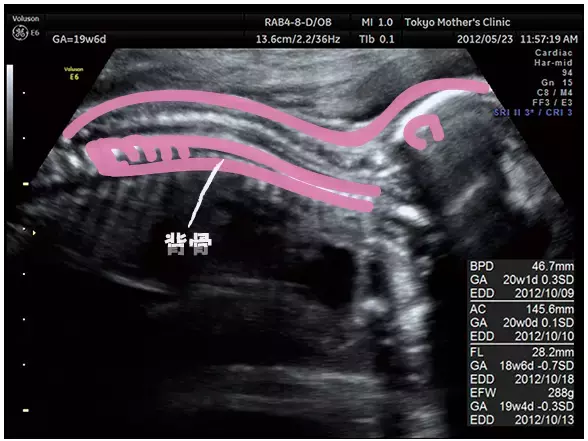

妊娠19週のエコー写真

身長が大きくなり、モニターに全身像が入りきらなくなってくるため、だんだんエコー写真も頭だけ、下半身だけ、とパーツごとになってきます。指の動きが複雑にできるようになり、ますます動きが人間らしくなるでしょう。また、胎盤の位置や子宮口の様子など、母体に異常はないかも確認しています。

力強い背骨がひとつひとつ白くくっきりと見えています。

右側が首、左側がおしり。

写真提供:東京マザーズクリニック